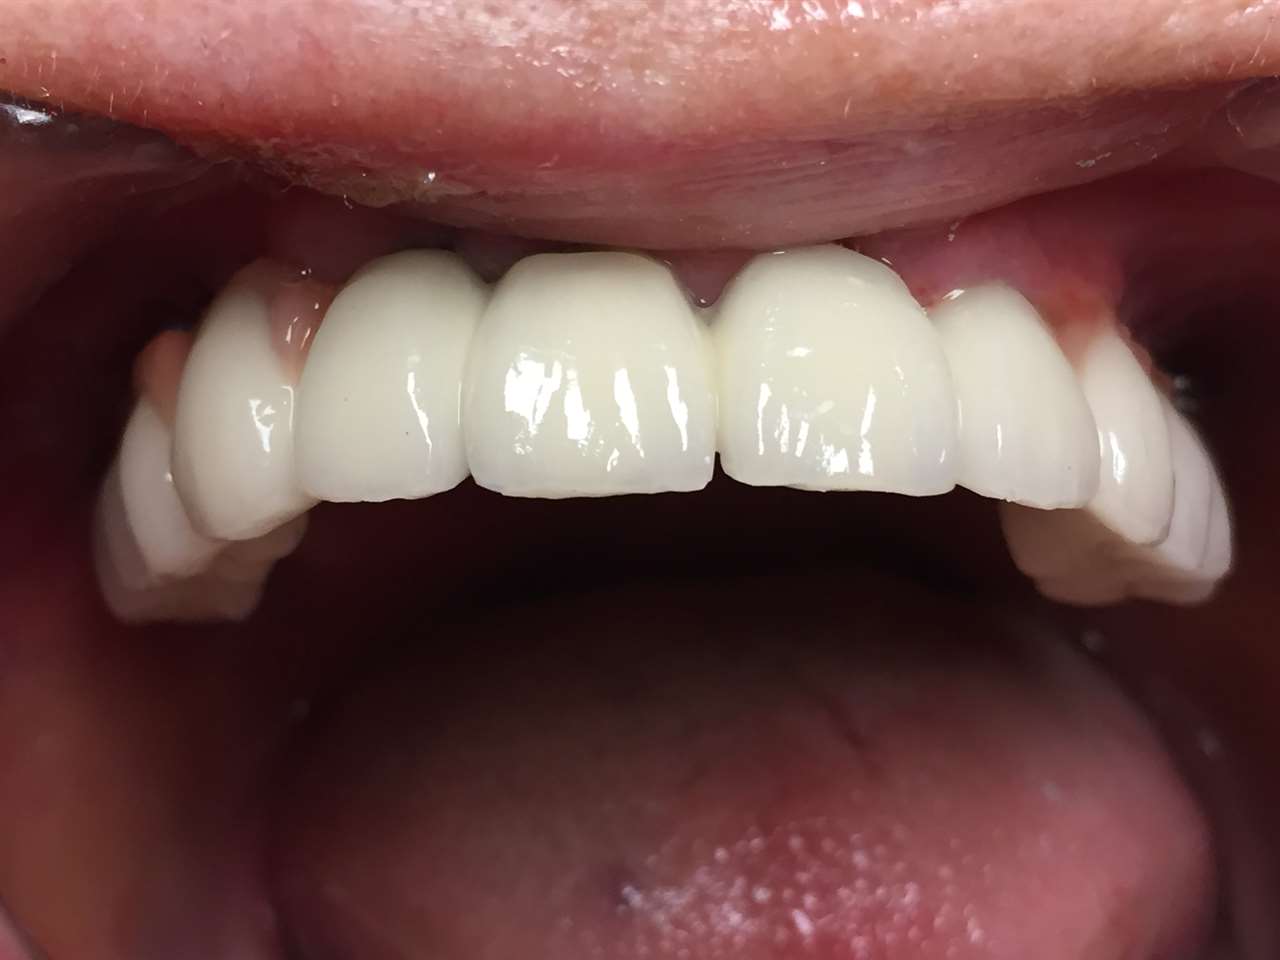

Elhanyagolt fogsor cseréje 2 nap alatt

2 nap alatt varázsoltuk ezt a szép esztétikus alsó, felső körhídat implantátumokkal megtámasztva a korábban elhanyagolt szájba. Az 1. nap 26 fogat távolítottunk el, mert annyira rossz állapotban voltak, és rögtön azonnal terhelhető IHDE svájci implantátumokat raktunk be, fentre 8, lentre 6 darabot. A sebeket összevarrtuk és intraorális szkennerrel digitális lenyomatot vettünk. 2 nap múlva pedig beragasztottuk a kész PMMA műanyag körhidakat. Dr. Kelemen Péter és a Symbion Fogtechnika munkája.